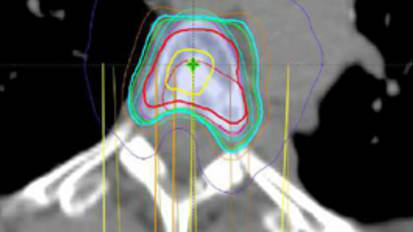

A research team at Baptist Health South Florida recently began enrollment in a randomized-controlled clinical trial exploring early radiation therapy as a prophylactic treatment for patients with asymptomatic or minimally symptomatic high-risk metastatic disease to the spine.New Brain-Mapping Tech at Baptist Health Miami Neuroscience Institute Provides Most Detailed Imaging